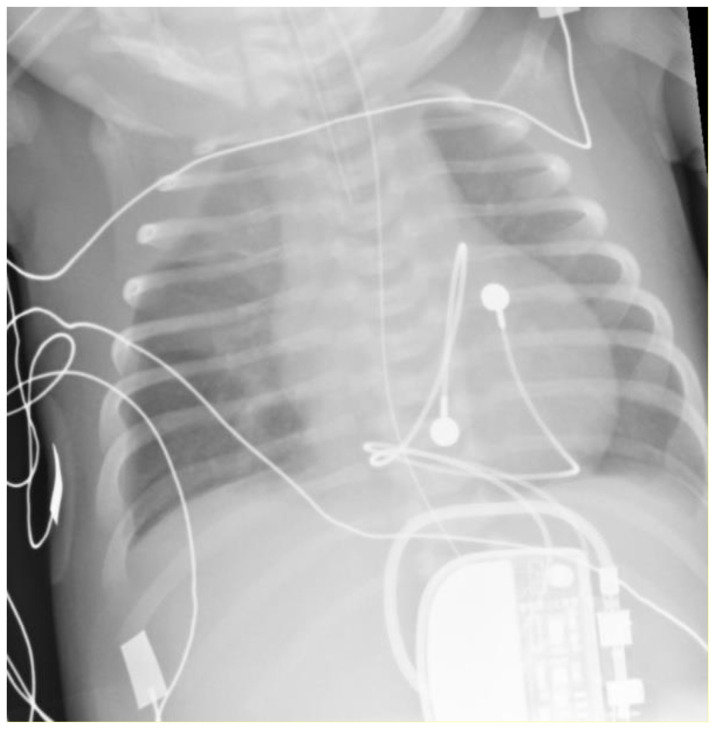

Cardiac strangulation is a rare but potentially lethal complication of epicardial pacemaker insertion. We present the case of a 9-year-old girl who was identified as having cardiac strangulation on routine follow-up for an epicardial pacemaker inserted on day 1 of life for congenital complete heart block (CCHB). The potential clinical presentations and risk factors for pacemaker strangulation are then discussed.